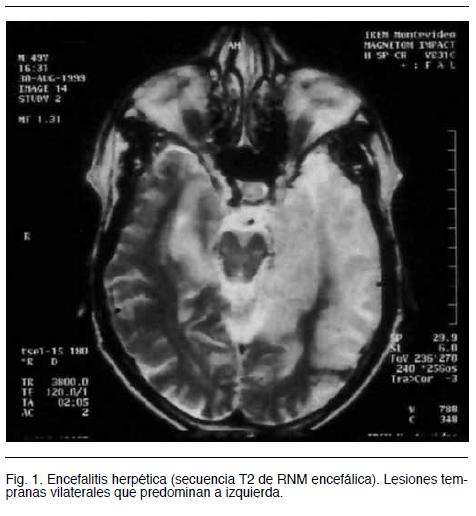

La RM en secuencia FLAIR muestra anomalías temporales en 90% de los adultos con EH a las 48 hs. del inicio de los síntomas, también son útiles la secuencia de difusión y la utilización de gadolinio, en general la lesión es bilateral predominando en alguno de los hemisferios. Muy raramente la RM es normal (menos de 10% tienen imagen normal con PCR +). En su plenitud las imágenes de RM muestran las lesiones en la parte medial del lóbulo temporal o en toda su extensión, cara orbito-frontal del lóbulo frontal y suelen ser bilaterales y asimétricas, raramente se pueden ver alteraciones en ganglios basales, tronco cerebral y cerebelo ( figura 1 y 2)

Estas imágenes en contexto clínico son altamente sugestivas del diagnóstico y cobra valor la bilateralidad, pero con predominio en un hemisferio. Otras enfermedades pueden tener una imagen similar, aunque algunas de ellas suelen respetar cierta simetría: encefalitis por HHV 6, encefalopatía mitocondrial (MELAS), encefalitis límbica paraneoplásica, síndrome de Ac anticanales de potasio, neurosífilis, etc. (5,16).